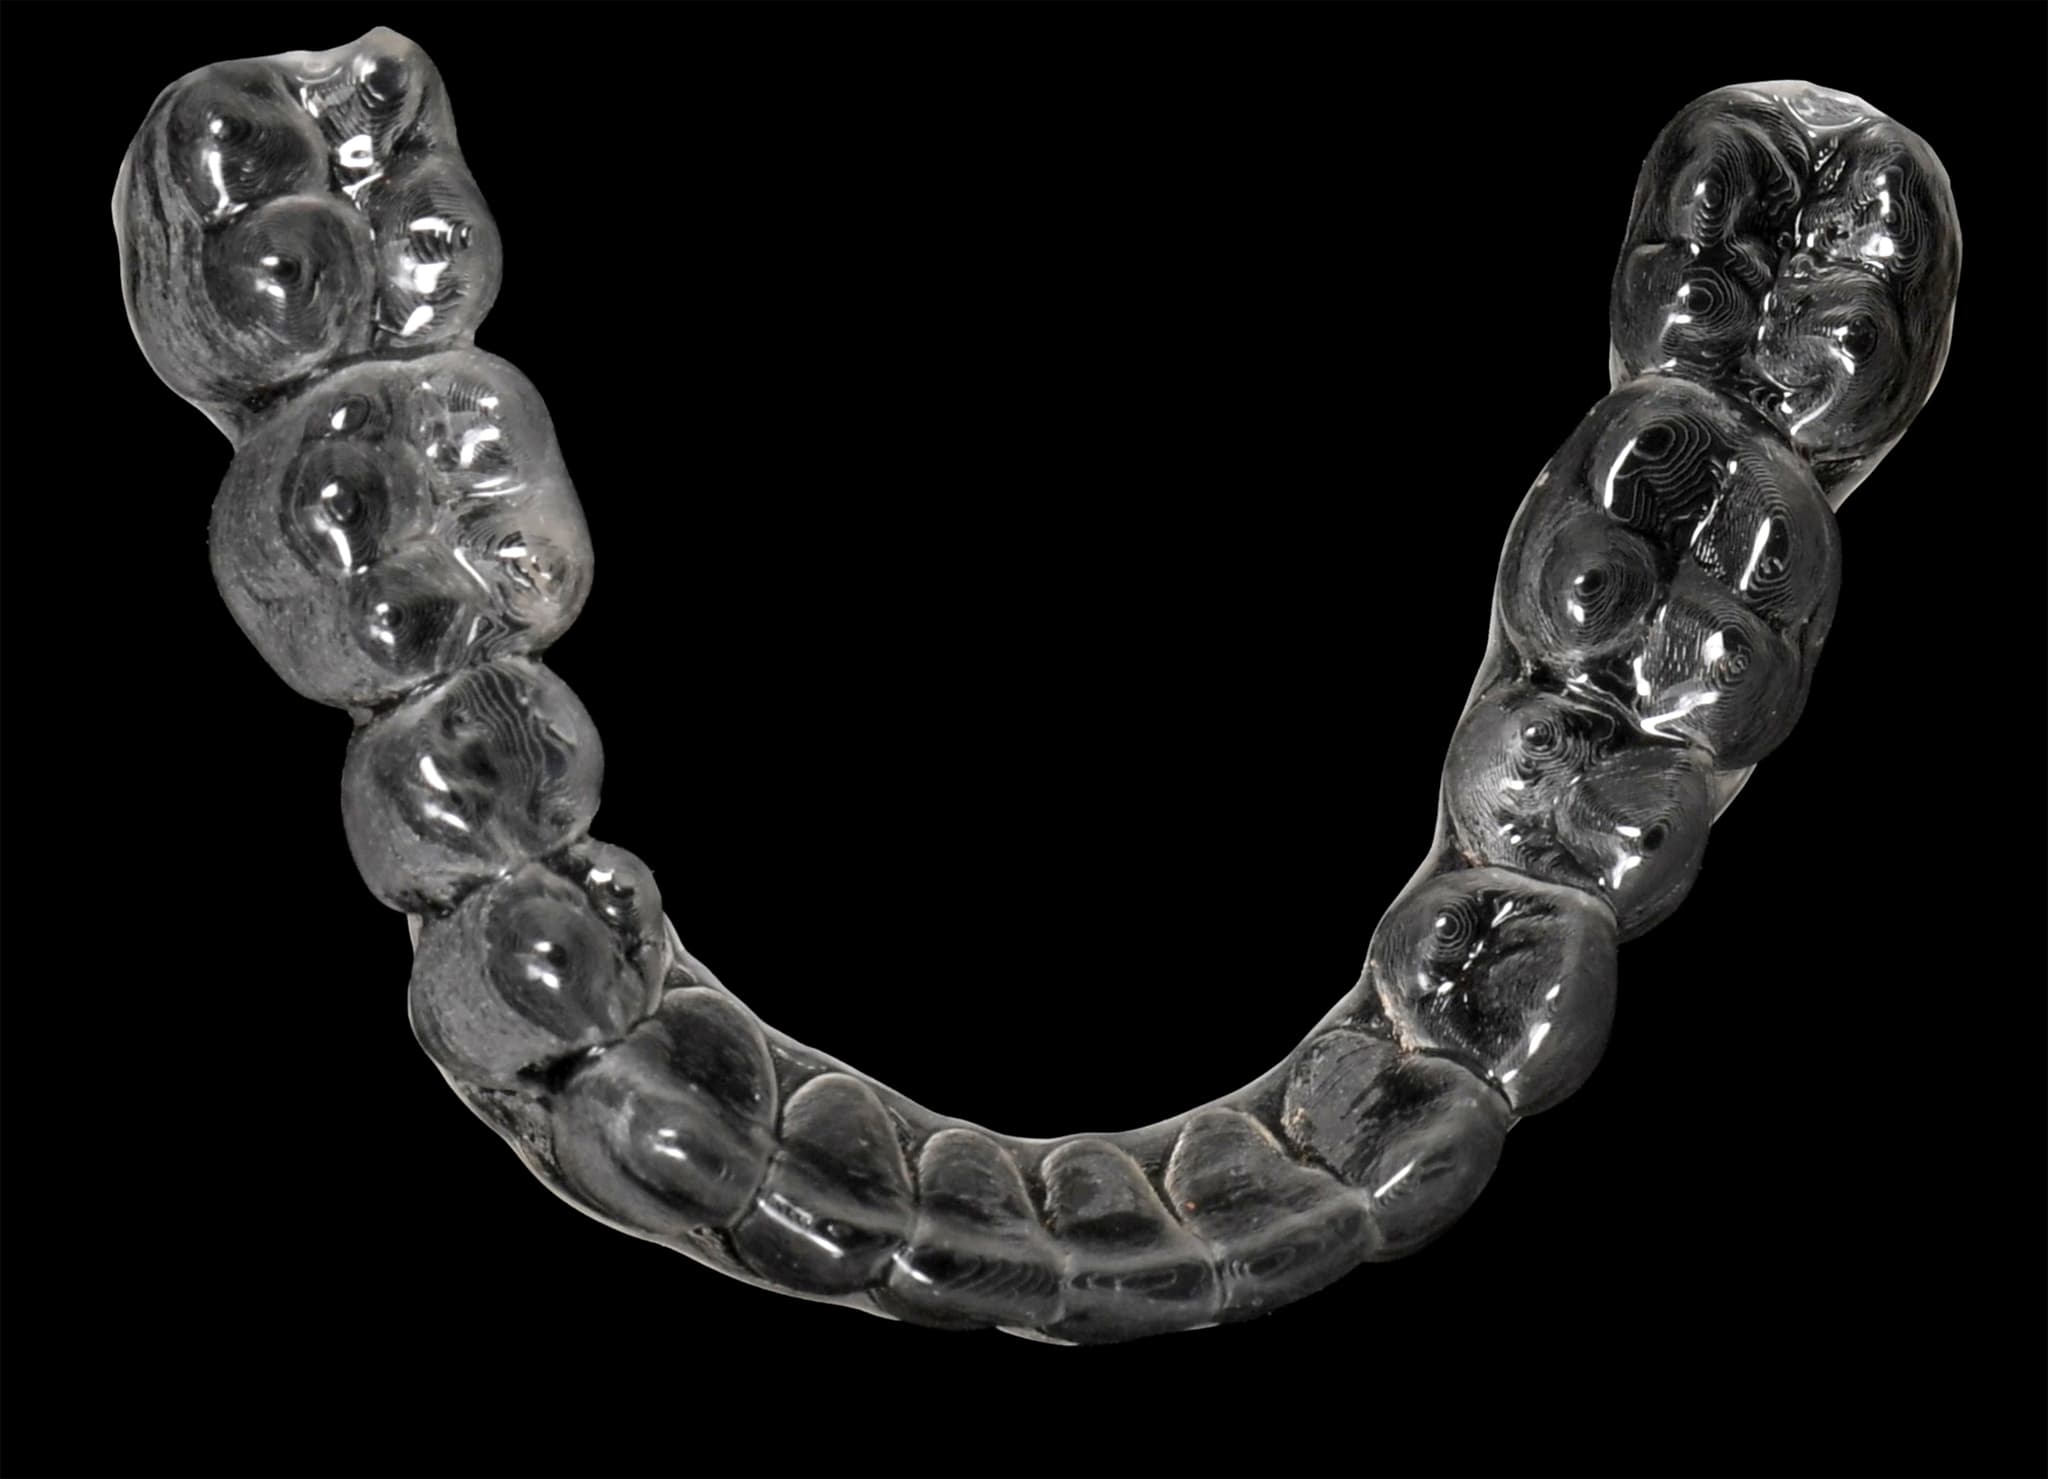

3. Finishing and Retention

From motion to stability.

After achieving the final position, we refine details like midlines, contacts, and smile arc. Retainers are designed based on the final digital blueprint. Because the full case is archived, future adjustments or restorations remain consistent with the original design—years later.

Technology-Enhanced Precision

From planning to retainers—all digital.

Using digital impressions, simulations, and 3D planning tools, we improve accuracy and predictability across every stage. This ensures a more comfortable treatment and allows easy future corrections, if needed.